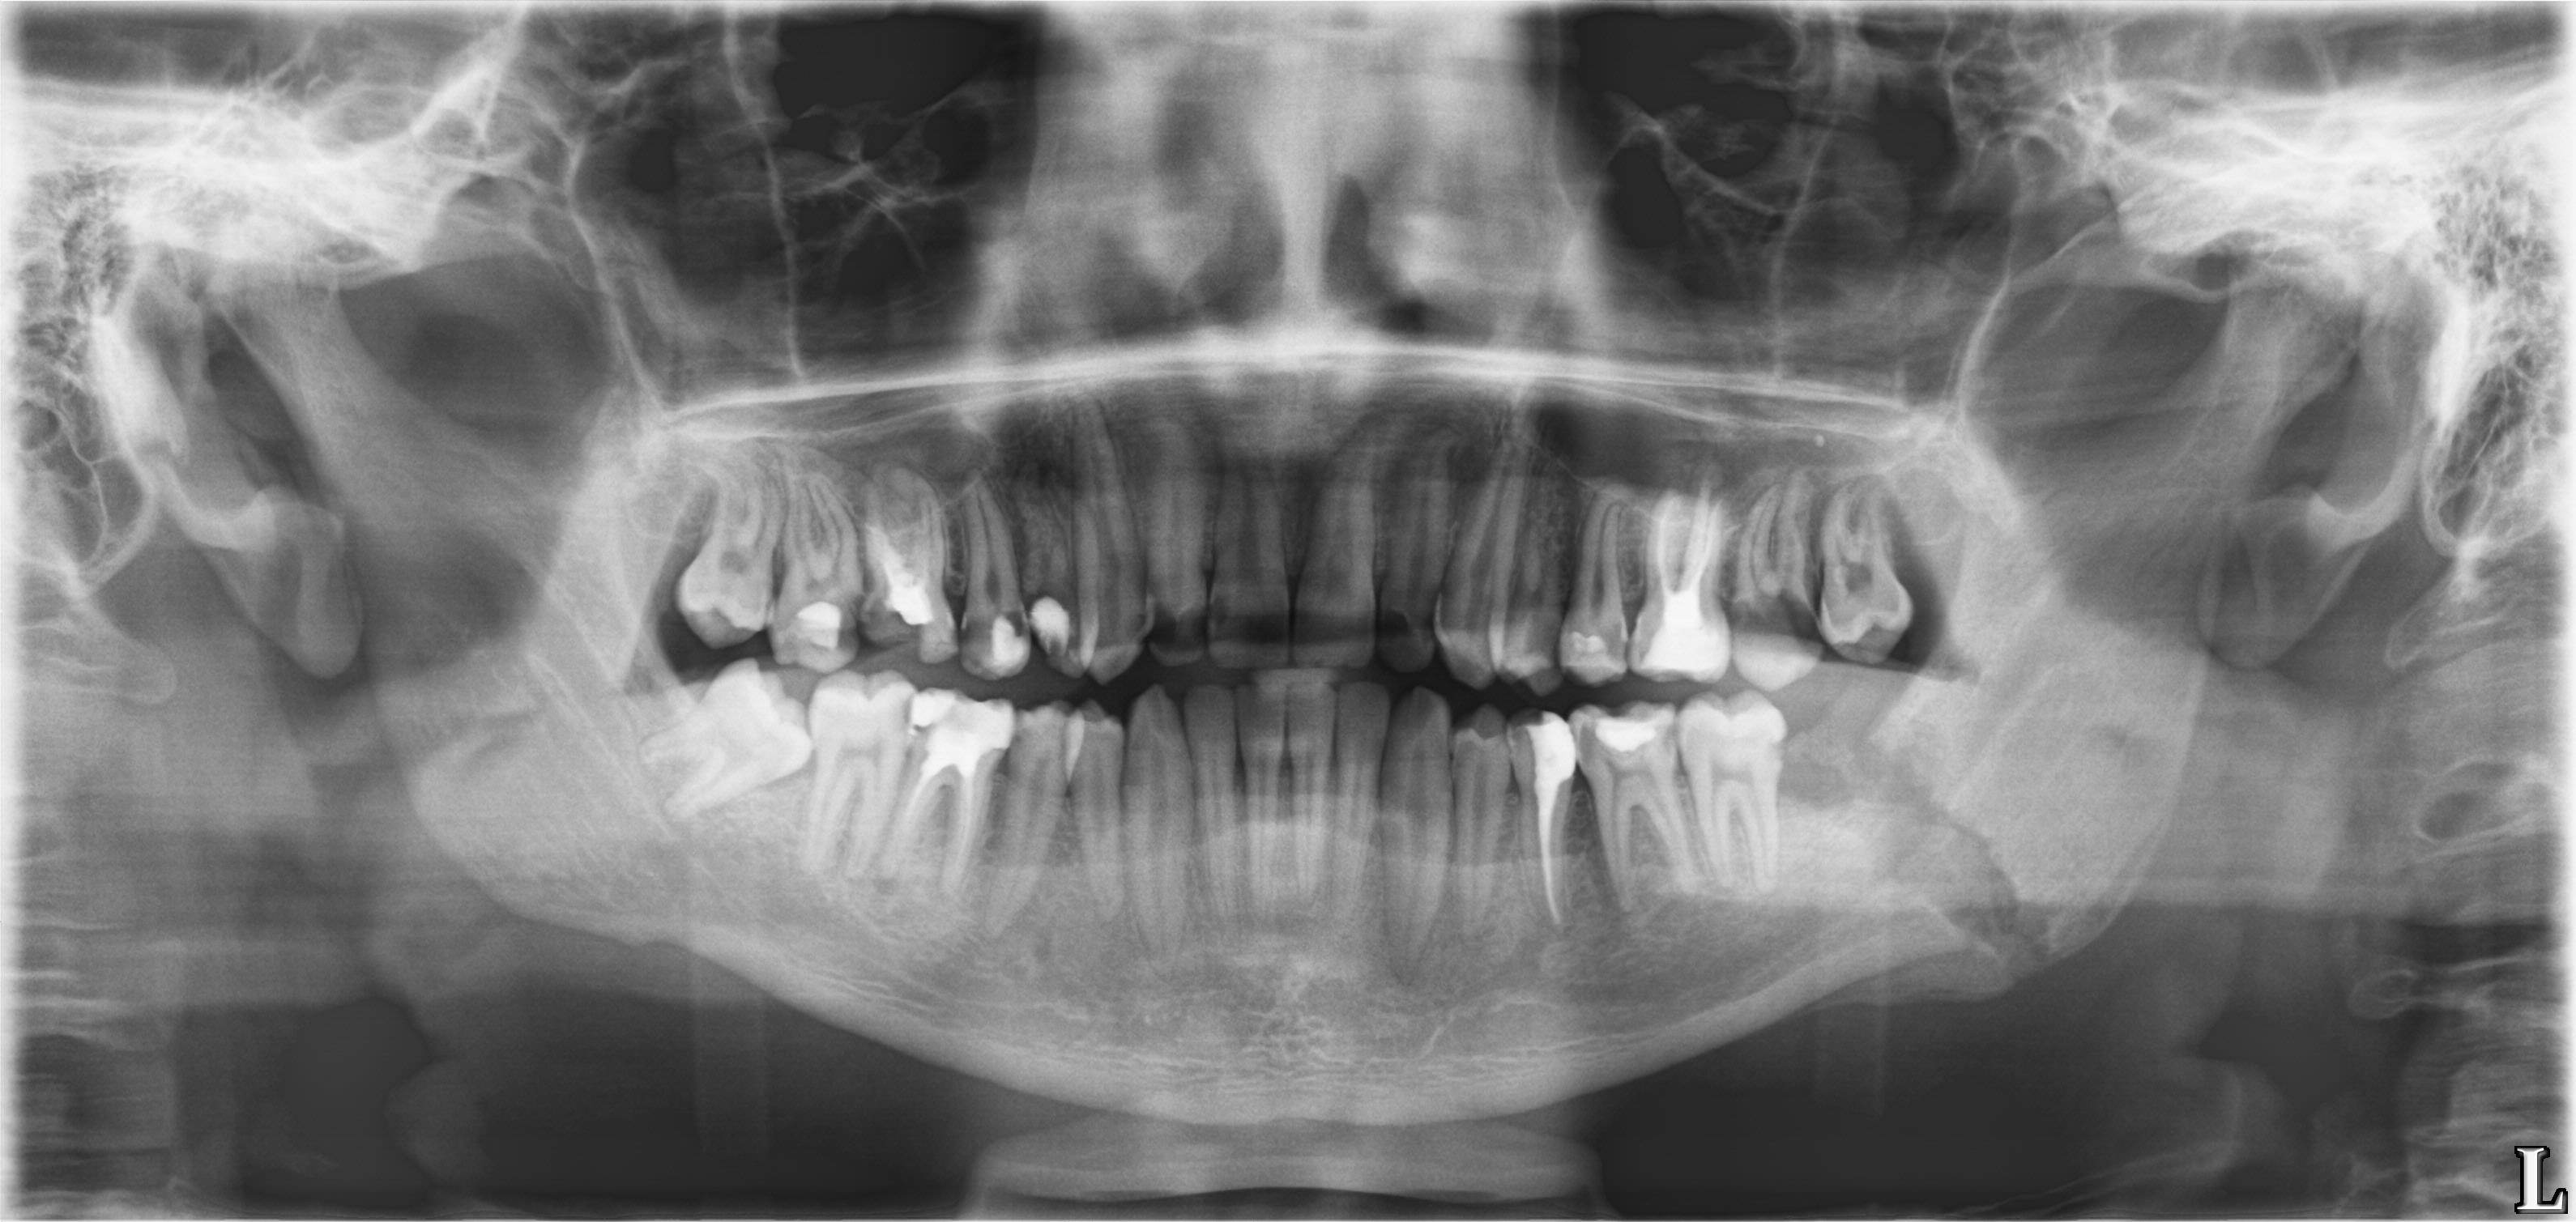

Молодой парень с припухлостью в области угла левой нижней челюсти.

Прислал ЛОР провести дифдиагноз между лимфаденитом и сиаладенитом.

--Травма была?

--ЫЫЫ. Месяц назад...